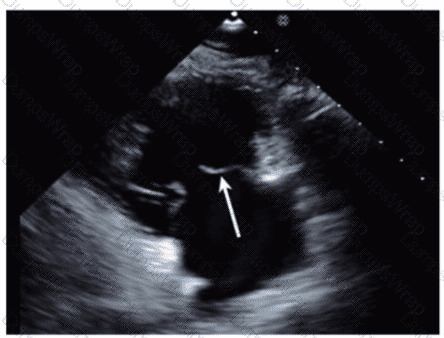

Which anatomic structure is represented by the arrow on this image?

DExplanation:

The echocardiographic image is a four-chamber view focusing on the mitral valve apparatus. The arrow points to the anterior leaflet of the mitral valve, which is typically more prominent, triangular in shape, and located adjacent to the aortic valve in the left ventricular outflow tract region.

The posterior leaflet of the mitral valve is generally smaller, has multiple scallops, and is located posteriorly relative to the anterior leaflet. The septal leaflet is part of the tricuspid valve on the right side of the heart. The "left leaflet" is a non-specific term and not an anatomical descriptor.

This differentiation between anterior and posterior leaflets is important for understanding mitral valve pathology and for interventions such as mitral valve repair. These features are clearly explained in echocardiography texts and ASE valve imaging guidelines【12:ASE Valve Imaging Guidelines†p.180-185】【16:Textbook of Clinical Echocardiography, 6e†p.200-205】.